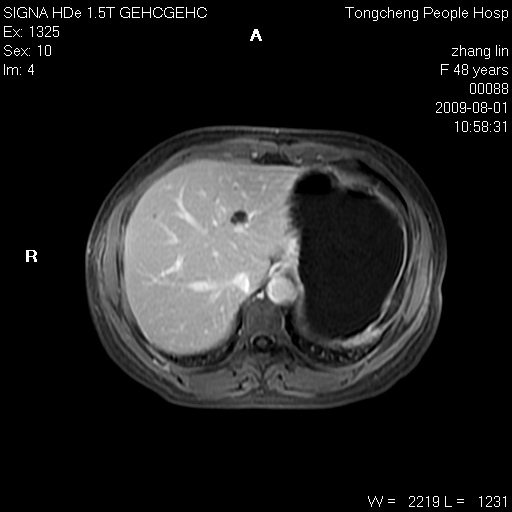

女,48岁。健康体检,彩超发现右肾占位性病变。平素健康。

临床诊断:右肾占位性病变,性质待定(囊肿?肿瘤?)。

上中腹部mr平扫+增强扫描,图像如下:

右肾上极见一类圆形病灶,t1wi呈等信号t2wi呈等高混杂信号,三期增强无强化,边界清---考虑囊肿出血。

同反相位均表现为等信号,病变无强化,考虑含蛋白的囊肿可能,弥散加权相或许有些帮助,